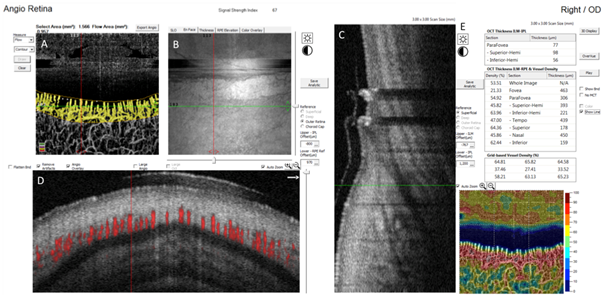

In this study, we performed OCTA scans in 10 healthy participants (6 men, 4 women, mean age 28.2 +/- 6.29 Table 2 shows demographic information of the subjects including age, sex and skin type. We scanned two subjects with deep brown skin, 3 subjects with white skin and 5 subjects ranging from light brown to moderately brown skin. Nailfold capillaries were successfully detectable in 100% of the OCTA scans. Figure 2 is an example of the OCTA scan obtained from subject 7 along with an image of the nailfold of the same digit using the traditional method for nailfold capillaroscopy. We measured the flow area and constructed a vessel density map using the built-in software of the instrument (RTVue XR, version 2016.2.0.35; Optovue Inc). Furthermore, we were able to obtain an automatic measurement of vessel density and flow area per individual scan as elucidated in Figure 3. Three-dimensional reconstructions were created and modified to allow an easy identification of the vessels and the surrounding anatomical structures. The front row of capillaries is easily identified in relation to the nail and the surface of the skin (Figure 4).

Figure 3 Optovue printout using the Angio Retina scan for nailfold capillaroscopy. (A) Area in mm2 manually delineated and automatically segmented for vessel area and flow area. (B, C, D) en face, longitudinal and axial cuts with red and green lines marking the corresponding location of the selected vessel. (E) Automatic measure of vessel density and thickness with colour coded map.